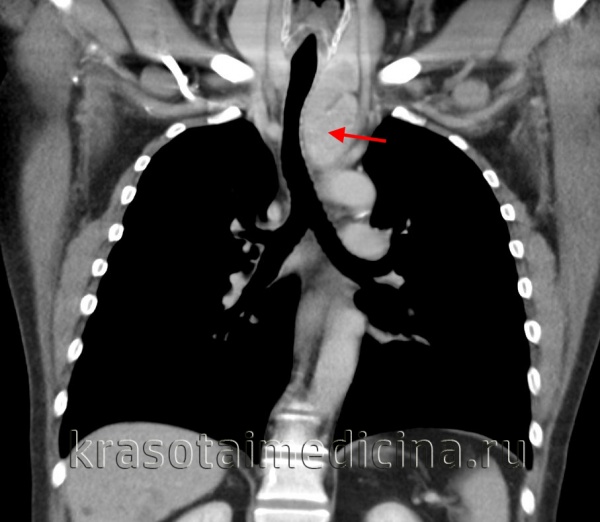

В верхнем средостении чаще всего обнаруживаются тимомы, лимфомы и загрудинный зоб; в переднем средостении - мезенхимальные опухоли, тимомы, лимфомы, тератомы; в среднем средостении - бронхогенные и перикардиальные кисты, лимфомы; в заднем средостении - энтерогенные кисты и неврогенные опухоли.

КТ ОГК. Массивное объемное образование верхнего средостения с объемным воздействием на трахею, исходящее из щитовидной железы.